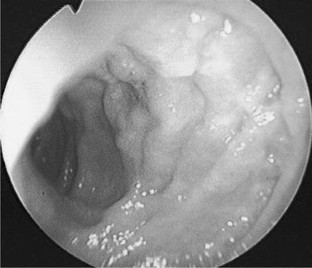

This report presents the case of a patient with Cowden syndrome who had arteriovenous malformations (AVMs) at the jejunum and the ileum and experienced intestinal bleeding. A 54-year-old Japanese male presented with general fatigue and melena. Endoscopic examinations showed gastrointestinal polyposis from the esophagus to the rectum. However, the site of bleeding was not identified. There were some papules on his face and neck. He also had macrocephaly and had multiple papillomas along the gum-line. These findings indicated a clinical diagnosis of Cowden syndrome. Enhanced computed tomography (CT) and angiography analyses indicated the presence of AVMs at the jejunum and the ileum. He was treated with partial resection of the jejunum and ileum including these two AVMs. This was a rare case of two AVMs involving the small bowel in a patient with Cowden syndrome. Enhanced CT was very useful and convenient for the detection of gastrointestinal AVMs in this case.

Fig. 4